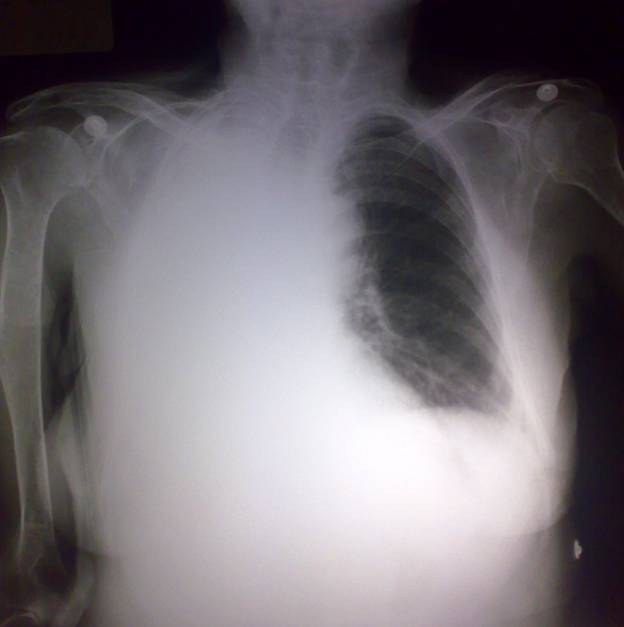

Chest Xray AP view

CT thorax